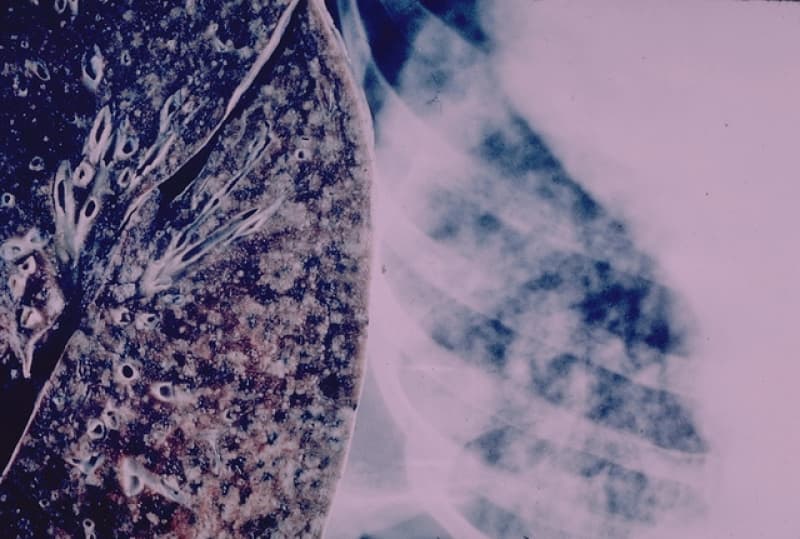

That is what life is like for people living with Cardio Obstructive Pulmonary Disease, or COPD. COPD is an umbrella term that includes conditions like emphysema, chronic bronchitis and chronic asthma.

Image: Yale Rosen on Flickr.